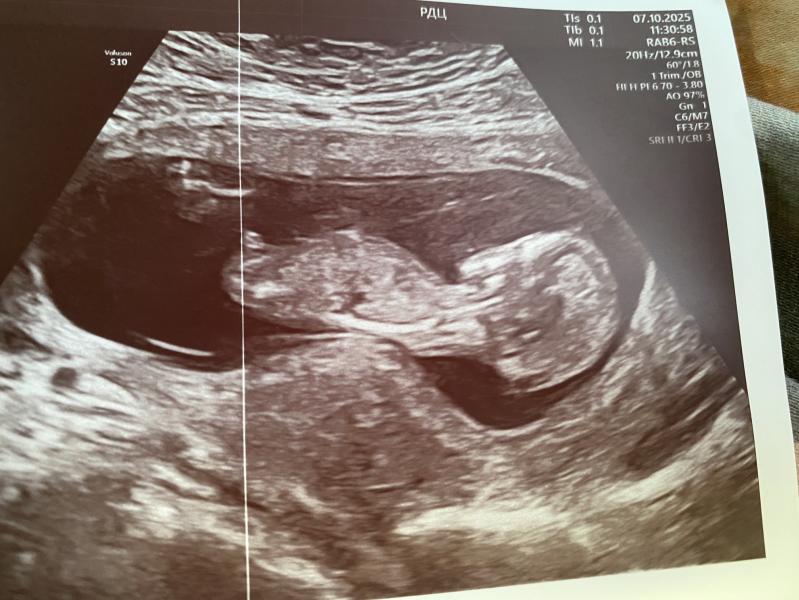

Это точно мальчик? Узи с неуверенностью показало пол

Это же у меня сто процентно мальчик?🥹🥹🥹🥹🥹

Врач с такой неуверенностью сказала, но я хотела мальчика, и услышала что мальчик, надеюсь не ошиблись🤍🥹

Половой бугорок смотрит вверх, скорее всего мальчик

С этого ракурса точно не определить пол.

срок 13 недель